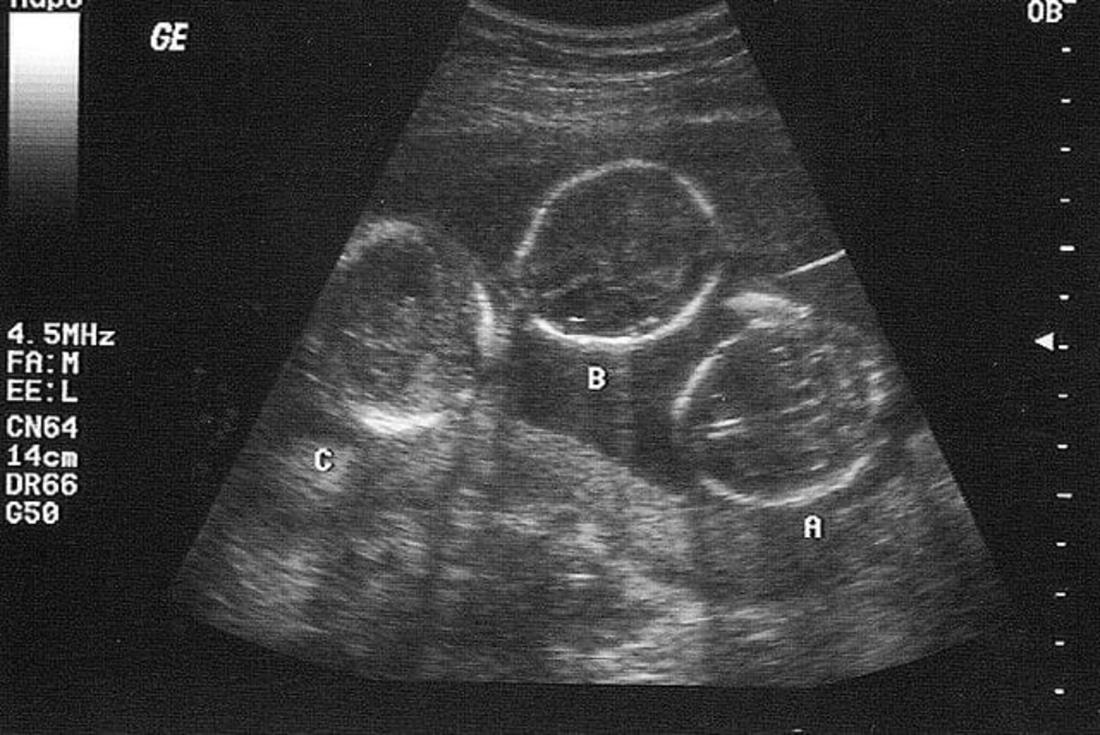

Πιο συγκεκριμένα, τρίδυμα γεννήθηκαν για πρώτη φορά στη χώρα μας προερχόμενα απο τον ίδιο πλακούντα, ανέφερε στην εκπομπή Περίμετρος της ΕΡΤ3.

Μάλιστα, σύμφωνα με τον γυναικολόγο, Νίκο Παπανικολάου, πρόκειται για τρίδυμα κοριτσάκια που προέρχονται από τον ίδιο πλακούντα, μονοζυγωτικά, φαινόμενο πολύ σπάνιο στην ιατρική βιβλιογραφία, καθώς όπως επισήμανε επειδή τρέφονται από τον ίδιο πλακούντα, υπάρχει η περίπτωση κάποιο από τα τρία να μην αναπτυχθεί σωστά και να συμπαρασύρει τα άλλα δύο.

Τα τρίδυμα μάλιστα, προέκυψαν μάλιστα από αυτόματη σύλληψη. Η συχνότητα εμφάνισης τέτοιας περίπτωσης στην ιατρική είναι μικρότερη του 1: 100.000 και στην ελληνική βιβλιογραφία δεν έχει εμφανιστεί αντίστοιχο τέτοιο περιστατικό.